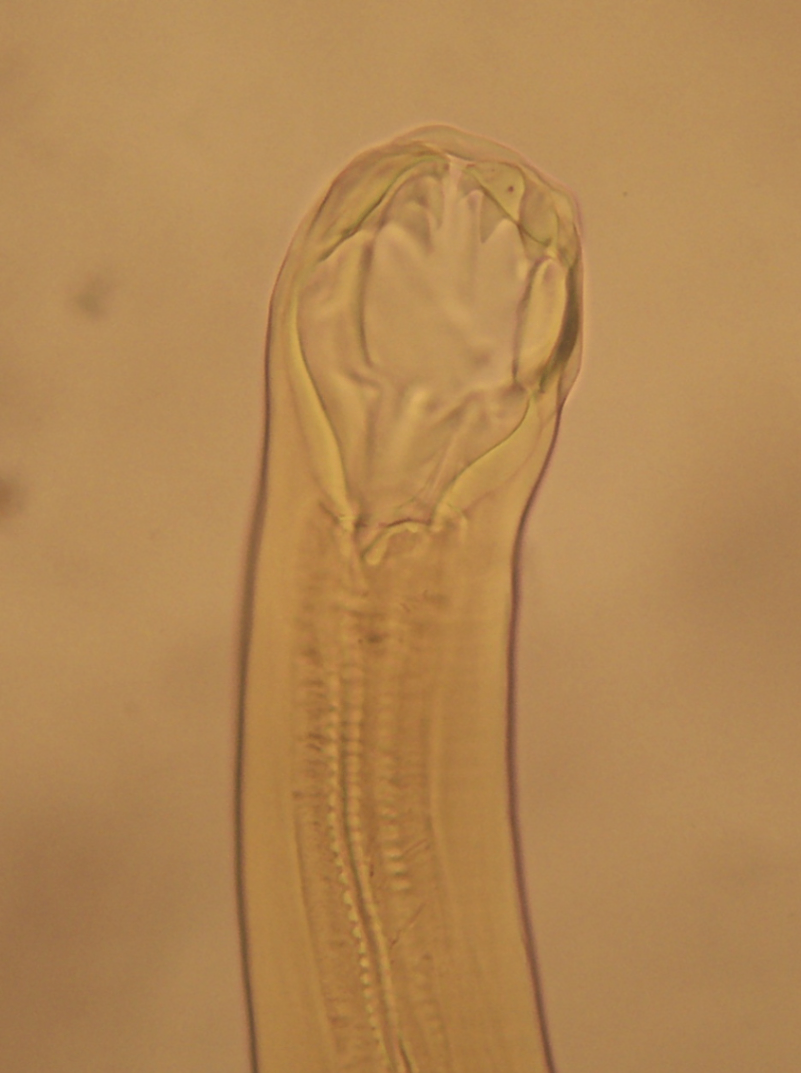

2) 치아와 같은 흡착기가 있어 hookworm이라 불린다.

Wikimedia Commons - File:Ancylostoma duodenale boca.jpg

사람에게 존재하는 대표적인 구충에는 두비니구충(Ancylostoma duodenale)과 아메리카구충(Necator americanus)이 있다.

구강 | 이빨(치아) 2쌍 | 절편형 절두판 |